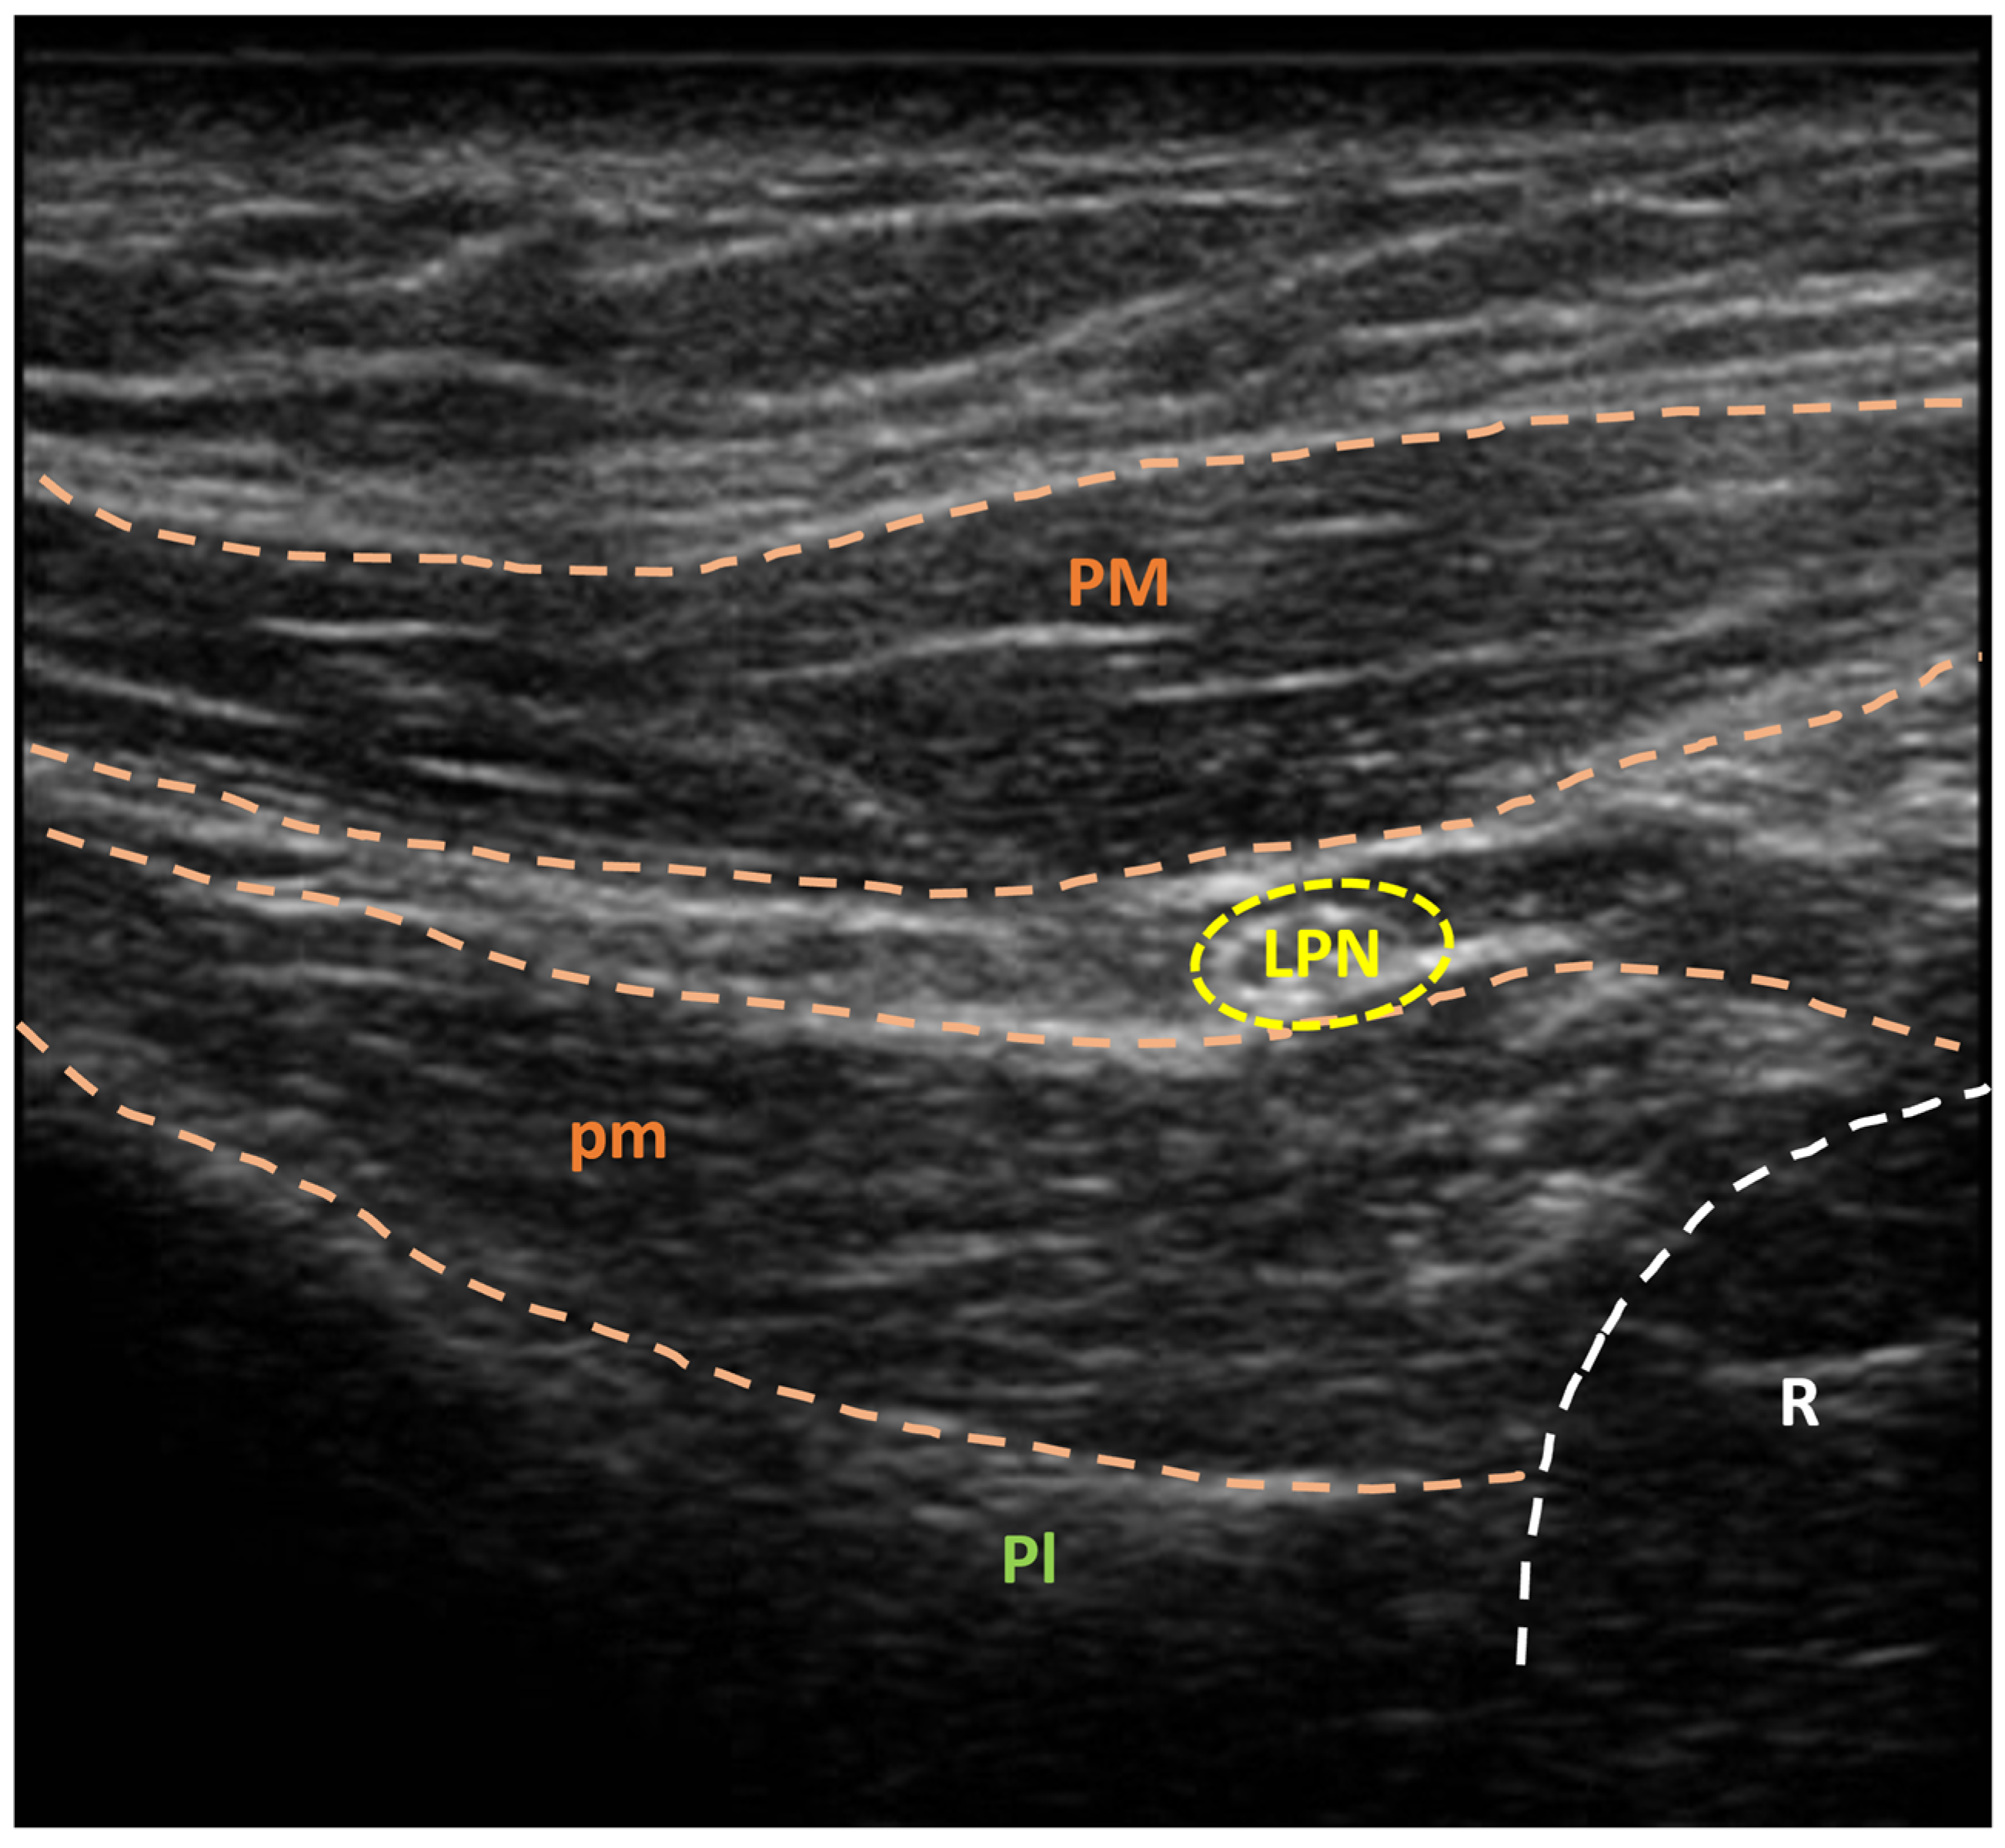

3.2. US-Guided Nerve Localization and Marking